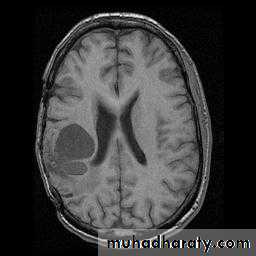

Brain Tumor Imaging

What’s changed between these images?

T1-weighted Sagittal

T1-weighted Axial

T2-weighted Axial